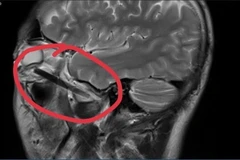

Các bác sỹ của Bệnh viện Đa khoa tỉnh Bình Dương đã phẫu thuật thành công lấy một phần chiếc đũa dài khoảng 6cm nằm sâu trong hốc mắt của người đàn ông.